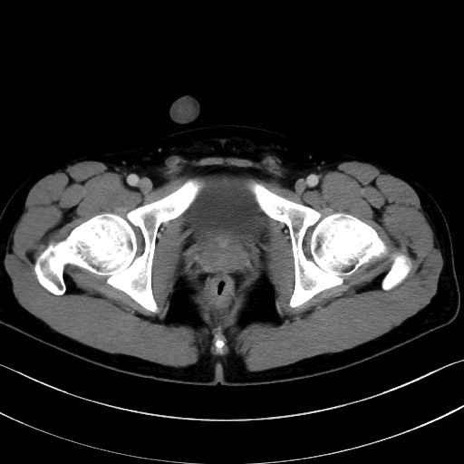

大腿直筋 (Rectus femoris)

外側広筋 (Vastus lateralis)

中間広筋 (Vastus intermedius)